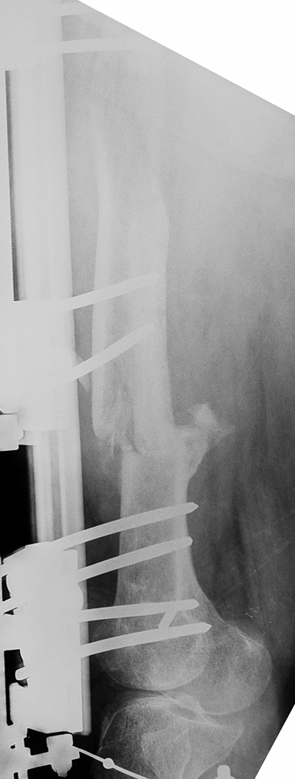

Vaka 1